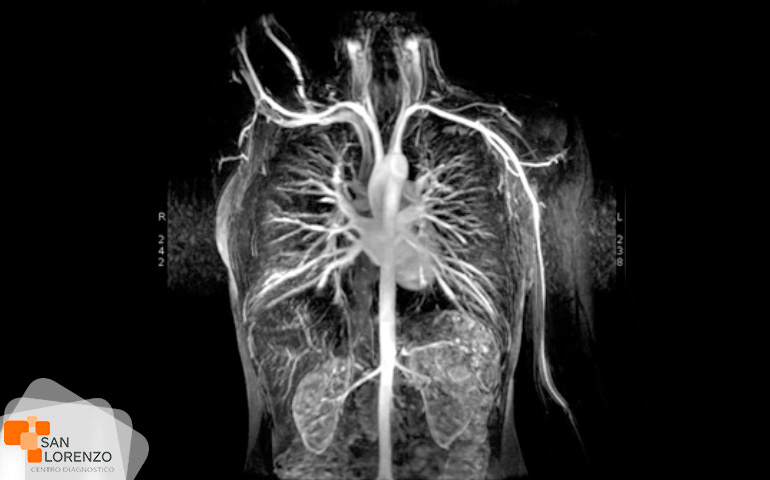

Cuando su médico especialista requiera una mejor visualización de los órganos, o estructuras internas normales o con lesiones, puede solicitar su examen con medio de contraste, éstos son sustancias indispensables para distinguir con mayor claridad áreas del cuerpo o tejidos circundantes que ayuden a diagnosticar condiciones médicas relacionadas con órganos específicos, vasos sanguíneos, o tejidos.

Frente a este requerimiento de su médico, hay que tener en cuenta que los contrastes endovenosos yodados, (usados en las TAC), o los paramagnéticos (usados en las Resonancias), pueden producir alergias o interferir en la función renal en algunos pacientes, como por ejemplo: pacientes monorrenos, con antecedentes de enfermedad renal obstructiva o cuya patología de base pueda implicar compromiso renal secundario; diabetes mellitus, mieloma múltiple, lupus e insuficiencia cardíaca, por lo tanto, en esos casos, todo examen imagenológico que requiera de contraste necesita contar previamente con un examen de creatinina.

Algunos de los exámenes relacionados con medios de contraste son: Angiotac, Urotac, TAC de abdomen y pelvis, TAC de cerebro en lo que se solicite contraste, y todas aquellas Resonancias magnéticas contrastadas.

Todos los exámenes de RM, TAC que requieran contraste tal como los mencionados anteriormente: Angiotac, Urotac, TAC de abdomen y pelvis, TAC de cerebro en lo que se solicite contraste y todas aquellas Resonancias magnéticas contrastadas.